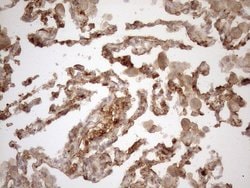

KRT16 Monoclonal Antibody (OTI1G1), TrueMAB™, OriGene

KRT16 is a member of the keratin gene family. The keratins are intermediate filament proteins responsible for the structural integrity of epithelial cells and are subdivided into cytokeratins and hair keratins. Most of the type I cytokeratins consist of acidic proteins which are arranged in pairs of heterotypic keratin chains and are clustered in a region of chromosome 17q12-q21. This keratin has been coexpressed with keratin 14 in a number of epithelial tissues, including esophagus, tongue, and hair follicles. Mutations in this gene are associated with type 1 pachyonychia congenita, non-epidermolytic palmoplantar keratoderma and unilateral palmoplantar verrucous nevus.Specifications

| Immunohistochemistry (Paraffin), Western Blot | |